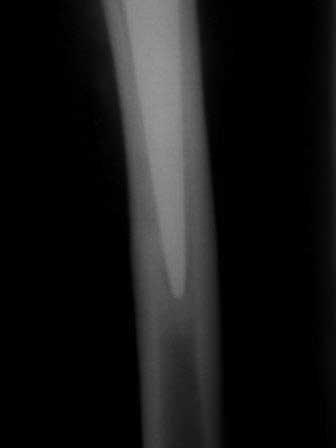

ниже снимок в 2008 году

далее снимок в 2009 году

далее снимок у меня на приеме

при этом, у этого пациента была СОЭ 20 мм в час, лейкоциты и формула лейкоцитарная в норме. Можно было пунктировать сустав, но мы этого не сделали и оказались правы: при вскрытии сустава на операции, сустав был сухой и жидкость для посева мы бы не получили.

Но все же, мы провели его лечение как инфицированного, учитывая анамнез: нагноение операционной раны грудины, после операции на сердце. К тому, боли в правом тазобедренном суставе он отметил после осложненной операции на сердце.